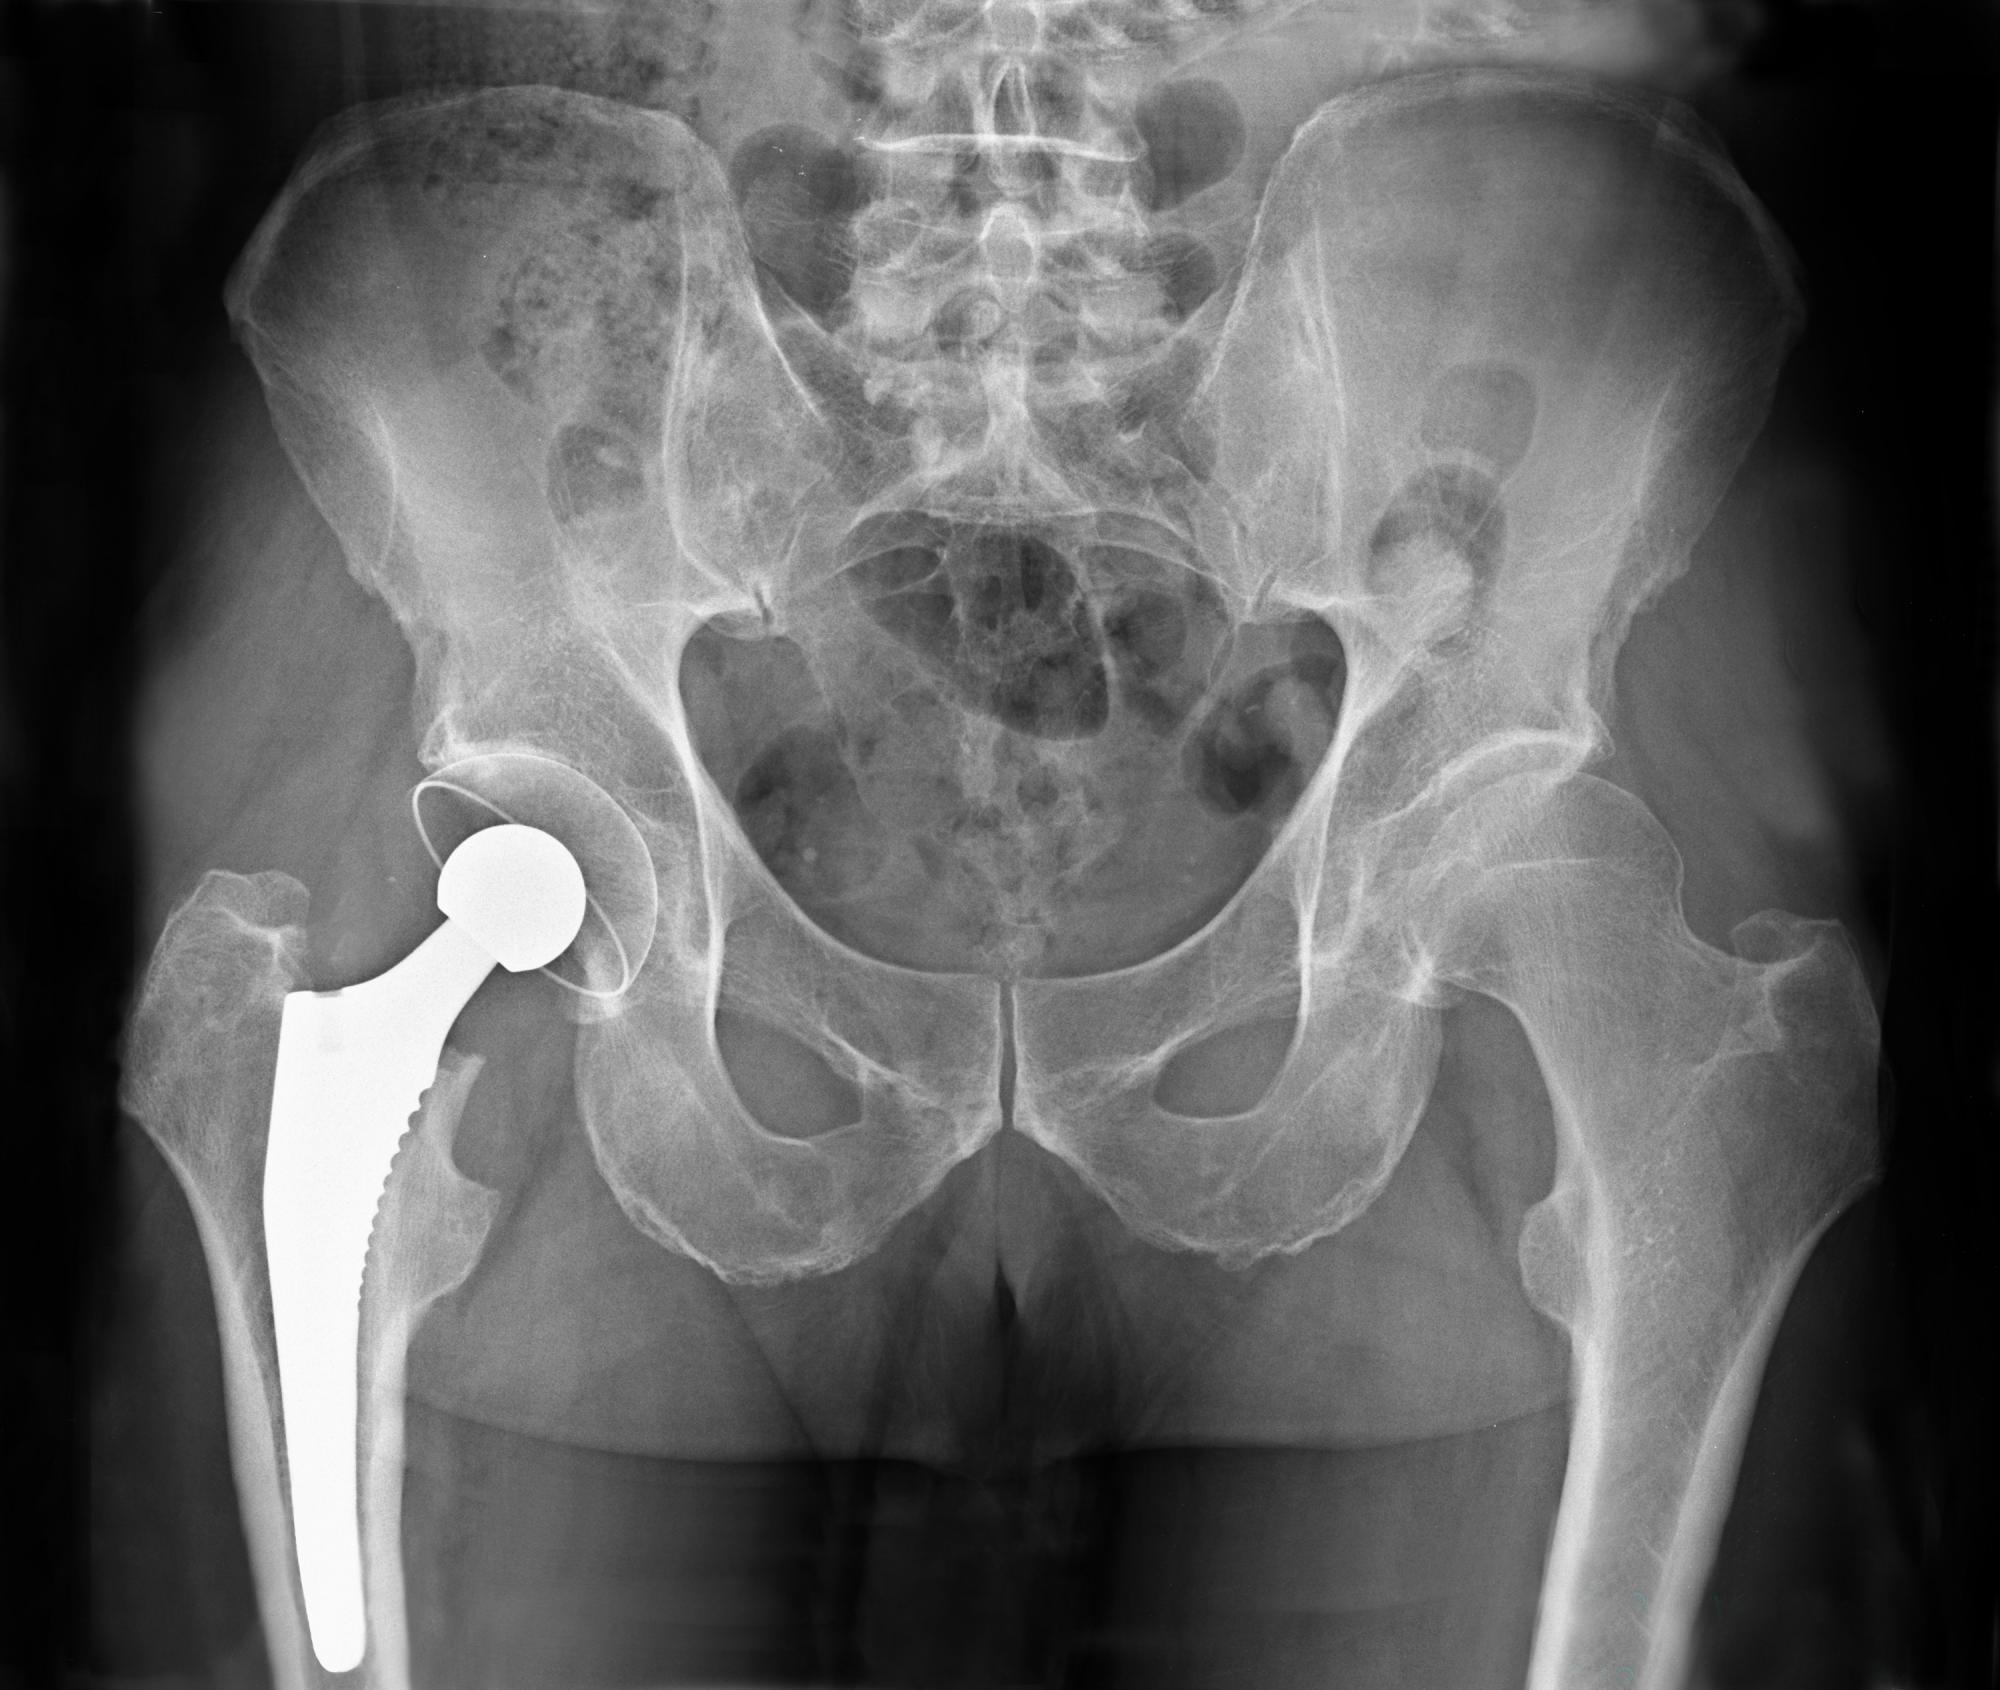

Les patients souffrant de nécrose avasculaire ou "ostéonécrose" (mort du tissu osseux) pourront peut-être éviter la pose d’une prothèse de hanche. L’opération, nécessaire pour retrouver de la mobilité au niveau de la hanche, pourrait bientôt laisser place à une simple injection.